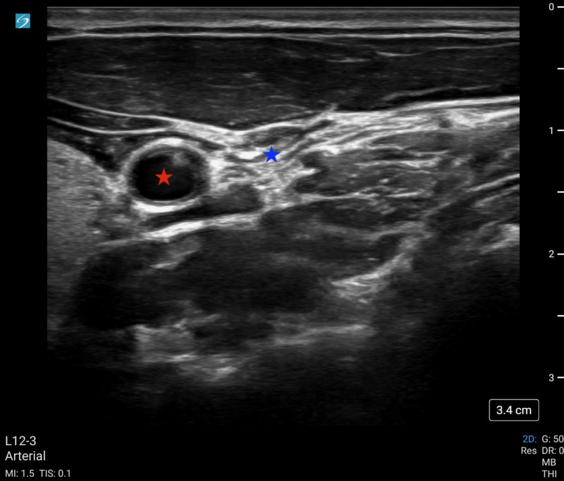

May2025Sonographic Fig 1 pocus cac.pngImage 1: POCUS-CAC with a fully compressed IJ (blue star) without compression of the common carotid artery (red star).

Compression

Perhaps the most accessible version of sonographic pulse check is the compression method. Using standard grey scale (B-mode) imaging, the operator uses the ultrasound probe to compress either the carotid artery or femoral artery until the accompanying major vein is completely collapsed, termed POCUS femoral artery compression (POCUS-FAC) or carotid artery compression (POCUS-CAC). In cases where ROSC has been achieved, the artery will not completely collapse and should display pulsatility.